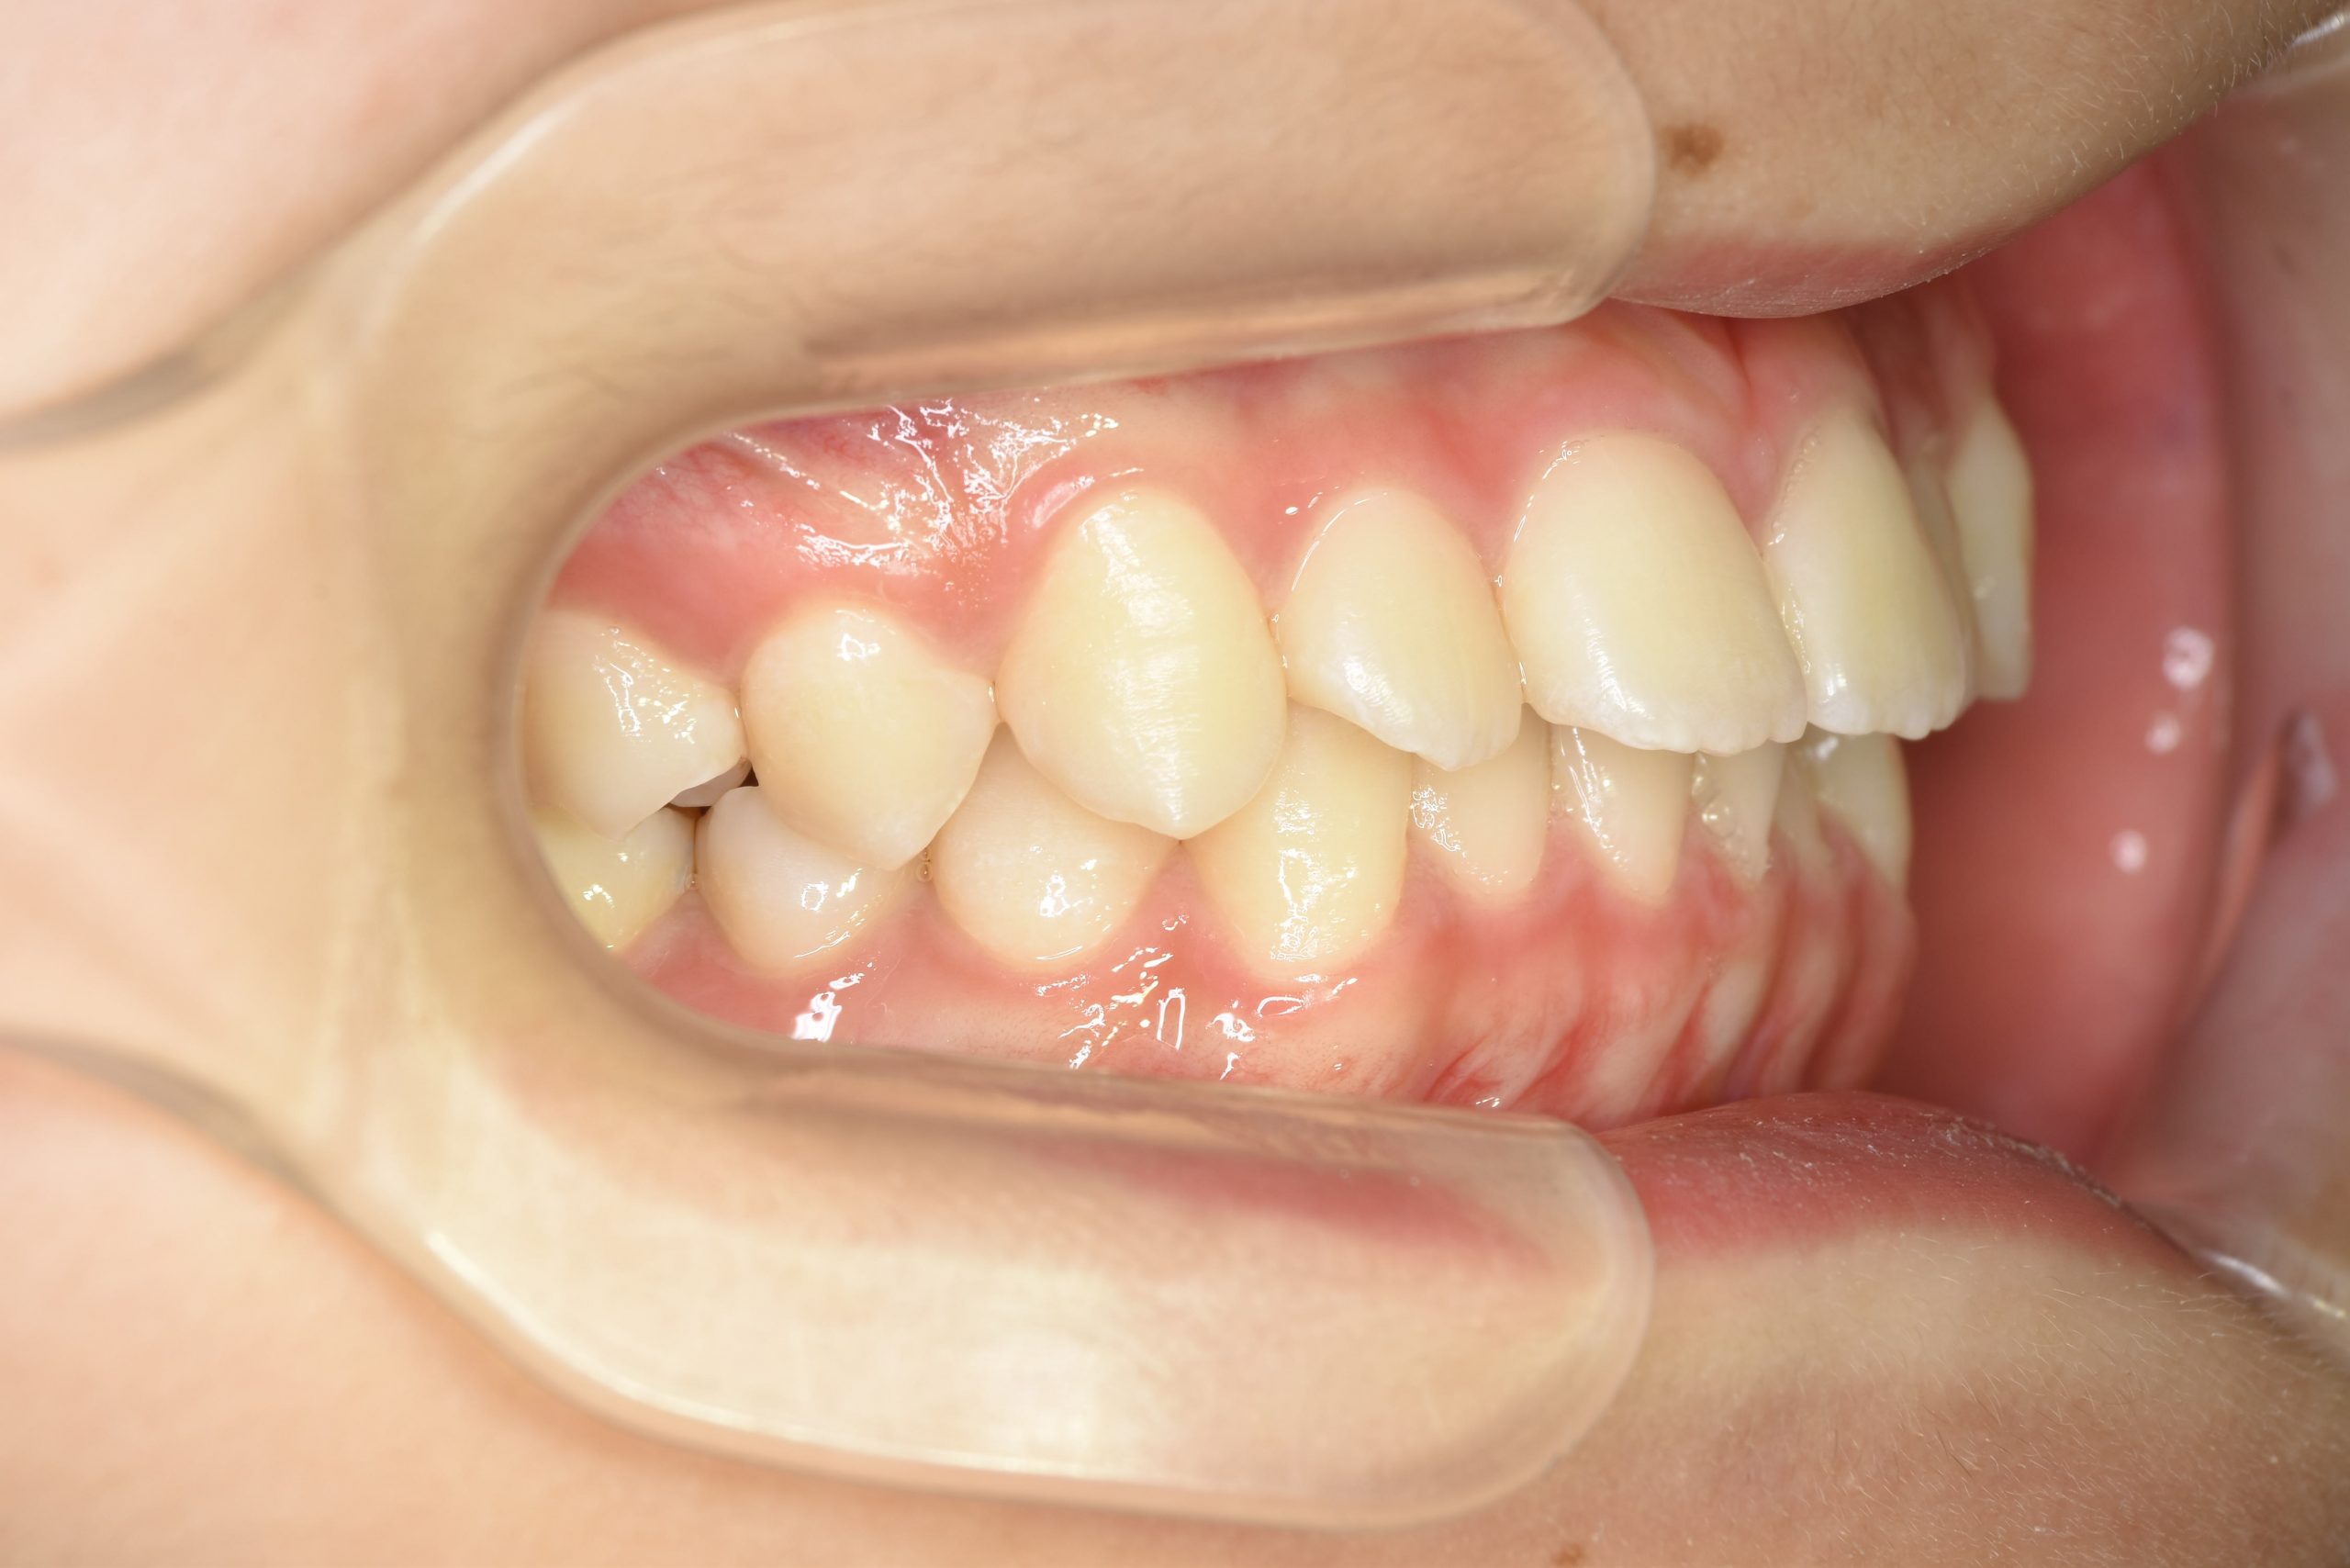

ビフォー

全顎ワイヤー矯正 症例_185

主訴 歯並び|横から生えている大人の歯

施術内容 小児矯正1期治療

治癒期間 4年間

費用 522,960円(税込)